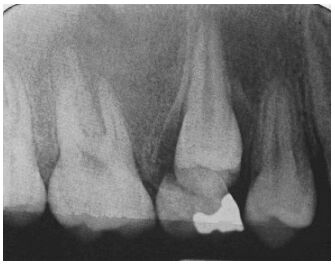

64.下列所附根尖周放射線影像(periapical film)中,其齒槽骨之放射線影像異於正常,最適切之描述為何?(A) 洋蔥皮狀影像(onion-skin appearance) (B) 陽光線狀影像(sun-ray appearance) (C) 羊毛棉花狀影像(cotton-wool appearance) (D) 毛玻璃狀影像(ground-glass appearance)